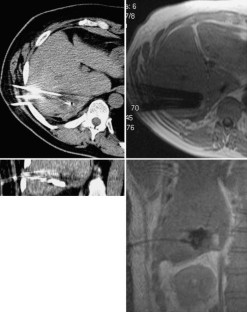

Im interdisziplinären Konsens wurden 182 Patienten (Lebertumoren: 131, andere Tumoren—Knochen, Lunge, weitere Tumoren: 51) mit 1–6 Applikatoren behandelt. Die Interventionen erfolgten in Kombination verschiedener Modalitäten (CT/MRT; CT/US) oder ausschließlich im geschlossenen MRT (1,5 T) mit direkt postinterventioneller MRT-Kontrolle.

Bei Lebertumoren wurde eine Ablationsrate von insgesamt 90,9% erzielt, die MRT erwies sich als optimale Methode zur Prozesssteuerung und direkten postinterventionellen Kontrolle. Die Komplikationsrate („major events“) betrug 5,4%. Bei nichthepatischen Tumoren ergab sich eine hohe technische Erfolgsrate mit organabhängig unterschiedlichem klinischem Erfolg.

Laser ablation was performed in 182 patients (liver tumors: 131, non hepatic tumors—bone, lung, others: 51) after interdisciplinary consensus was obtained. The procedure was done using a combination of imaging modalities (CT/MRI, CT/US) or only closed high field MRI (1.5 T). All patients received an MRI-scan immediately after laser ablation.

In 90.9% of the patients with liver tumors, a complete ablation was achieved. Major events occurred in 5.4%. The technical success rate of laser ablation in non-hepatic tumors was high, clinical results differed depending on the treated organ.

Abb. 1

Abb. 2